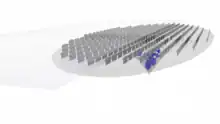

The lens capsule is a transparent membrane that surrounds the entire lens. The capsule is thinnest at the posterior pole with approximate thickness of 3.5μm. Average thickness at the equator is 7μm.[5][9] Anterior pole thickness increases with age from 11-15μm. The thickest portion is the annular region surrounding the anterior pole. This will also increases with age (from 13.5-16μm).[10] The ligaments suspending the lens form attachments in the equatorial area and more so just to the front and back of the equator.[11] There are tens of thousands of these ligaments in a mouse lens and for the most part they appear to connect directly to the lens capsule.[12]

As the lens grows throughout the life of most vertebrates the capsule is required to grow as well.[13] As shown in the accompanying micrographs and diagrams some ligament anchors have associated cells where they connect to the lens capsule. These cells have periodic cellular processes penetrating the capsule.

The structures in the images are consistent with the laying down of new capsular material required for growth. Even though the capsule is a highly elastic structure,[14] it contains no elastic fibers. Elasticity is because of the thick lamellar arrangement of the collagen fibers.[10]